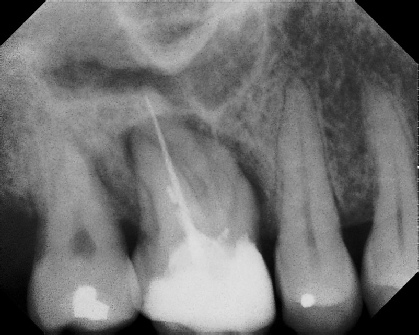

COMPLICATED ANATOMY LARGE LESIONS CALCIFIED CANALS PERFORATION / RESORPTION SEPARATED INSTRUMENTS SURGICAL CASES RETREATMENT / pOST REMOVAL OPEN APICES ACCESS THRU CROWNS Root Canal Case Portfolio